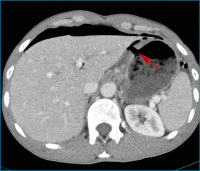

Abbildung 1: Das axiale CT-Bild zeigt ein perforiertes Ulkus des Magens (Pfeil).